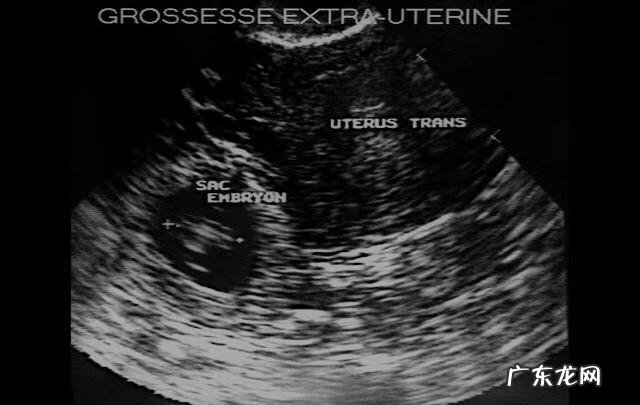

一、宫外孕是什么?顾名思义,宫外孕就是指受精卵没有在应该去的子宫里着床生长,而是去了宫腔之外的地方,所以又叫作异位妊娠 。随着胚胎的生长,会对腹腔内的器官造成挤压损害 。宫外孕有95%发生在输卵管内,胚胎会将输卵管撑裂出血,导致休克、昏厥甚至死亡,是孕产妇死亡的主要原因之一 。